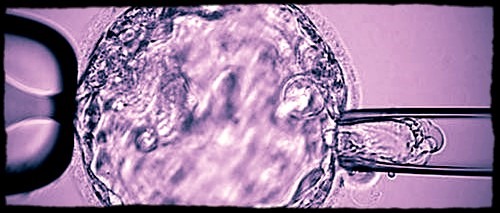

Biopsy procedure of a blastocyst

Biopsy procedure of a blastocyst (day-5 embryo) for subsequent preimplantation genetic testing